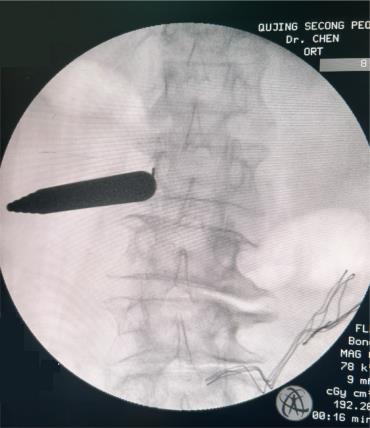

• 单通道非同轴脊柱内镜经椎间孔外入路(椎板外切迹)治疗极外侧椎间盘突出症的临床疗效观察

摘要:目的 观察单通道非同轴脊柱内镜经椎间孔外入路(椎板外切迹)治疗极外侧椎间盘突出症(FLLDH)的临床疗效。方法 回顾性分析2022年5月-2024年5月该院收治的,行单通道非同轴脊柱内镜经椎间孔外入路(椎板外切迹)治疗的FLLDH患者70例。于术前和术后,评估腰腿疼痛程度、腰椎功能和临床疗效。结果 相较于术前,术后3 d和3个月,患者下肢视觉模拟评分法(VAS)评分、腰部VAS评分、Oswestry功能障碍指数(ODI)、数字分级评分法(NRS)评分和Roland-Morris功能障碍问卷(RMDQ)评分明显降低,日本骨科协会(JOA)评分明显升高,差异均有统计学意义(P < 0.05);改良MacNab评分标准显示,末次随访时的优良率为94.28%。结论 单通道非同轴脊柱内镜经椎间孔外入路(椎板外切迹)治疗FLLDH,能明显改善患者腰腿疼痛和腰椎下肢功能,其具有创伤小、易操作、安全性高和疗效好等优点,值得在临床推广应用。